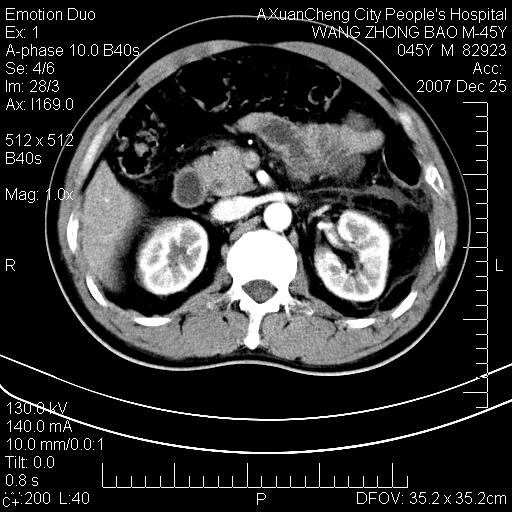

以下是引用qiuleiyu在2007-12-25 18:14:00的发言:[br]胰腺增大,周边渗出改变,肾前筋膜明显增厚,示少量积液.胆囊壁毛糙,周边少许渗出,胆总管壁厚,异常强化,然扩张不明显.结合病程急短;考虑;胆管炎,胆囊炎,胆源性胰腺炎可能大,请结合实验室检查及随访.

以下是引用lisihao在2007-12-25 14:23:00的发言:[br]急性水肿型胰腺炎[br]依据:1、胰腺弥漫性肿大,边缘稍毛糙;[br] 2、双侧肾周筋膜增厚,尤以左侧为甚(重要征象)[br] 3、双侧后胸膜增厚(刺激性炎症);[br] 4、结合病史,查血尿淀粉酶应该可以确诊。